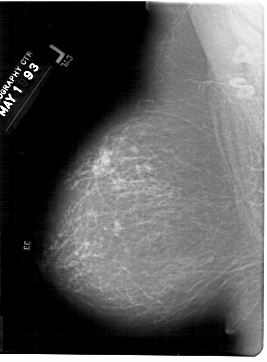

A_1421_1.LEFT_MLO

LEFT_MLO LINES 6871 PIXELS_PER_LINE 5056 BITS_PER_PIXEL 12 RESOLUTION 43.5 NON_OVERLAY